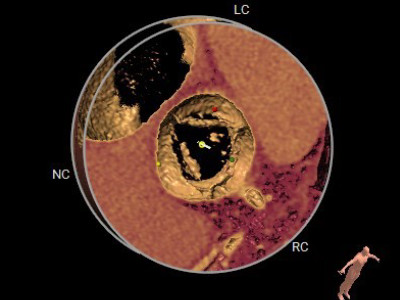

瓣叶开放3D图